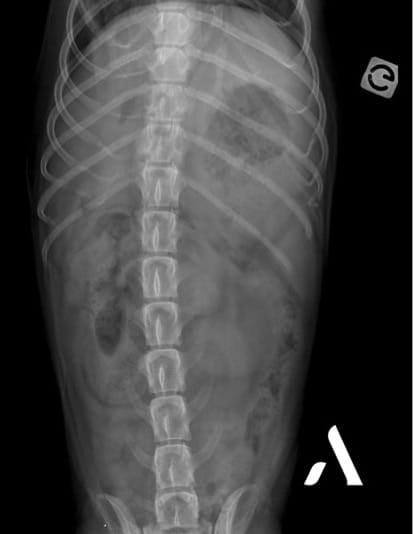

Un service imagerie toujours encadré par un spécialiste tout au long de l’année.